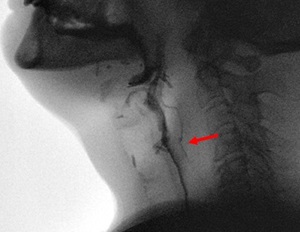

| Before Esophageal Dilation Example | After Esophageal Dilation Example |

|---|---|

![]() |